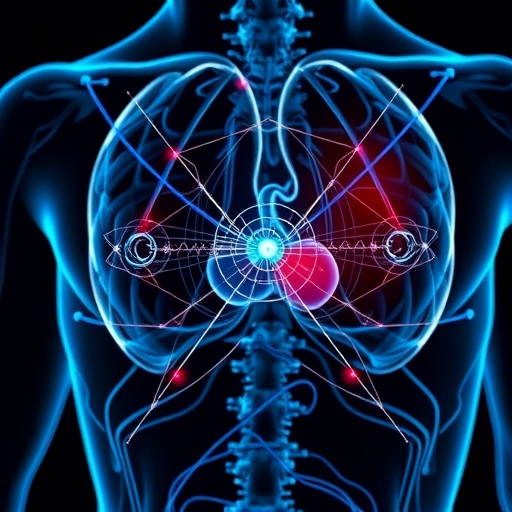

Prostate cancer detection historically hinges on a multipronged approach. The prostate-specific antigen (PSA) blood test serves as an initial screening method. However, elevated PSA levels are not exclusively indicative of cancer, often leading to unnecessary biopsies. As the frequency of PSA testing increases, so does the demand for accurate follow-up diagnostic procedures. Magnetic resonance imaging (MRI) has emerged as a critical tool, providing detailed visualization of the prostate and surrounding tissues. Yet, interpreting these MRIs is labor-intensive and subject to variability in human judgment, underscoring the need for AI-based solutions like PROVIZ.

The technological leap represented by PROVIZ relies on deep learning frameworks trained on extensive datasets containing annotated prostate MRI scans. These algorithms extract nuanced imaging features often imperceptible to human observers, enabling detection of lesions with greater sensitivity and specificity. By quantifying radiomic data—such as texture, shape, and signal intensity—AI models can correlate imaging phenotypes with histopathological outcomes, guiding clinical decisions on biopsy necessity and optimizing the biopsy site selection process.

The current landscape of medical imaging diagnostics grapples with burgeoning volumes of data, straining human resources and risking diagnostic variability. AI technologies like PROVIZ present a solution to these challenges by reducing workload and facilitating earlier, more precise diagnosis. This paradigm shift has the potential to alleviate bottlenecks in healthcare systems while improving patient outcomes through timely intervention.